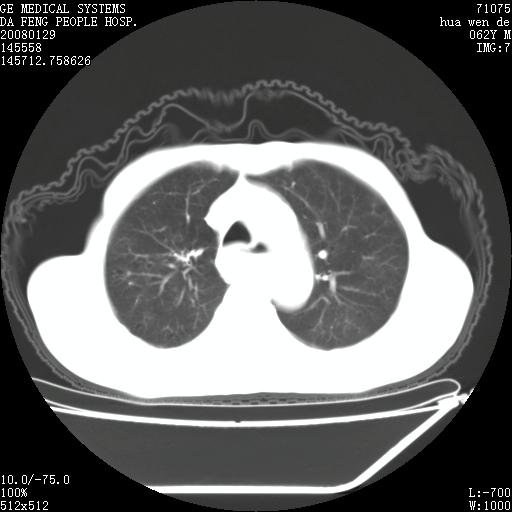

男性,67岁。作肺部检查时发现

理由:1、右上肺内病灶,空洞形成,有液平。

2、肺内多处炎症。

1.整个食管扩张,未见明显占位性病变,贲门区亦未见明显占位病变,考虑:贲门失驰缓症;

2.右上肺病变边缘可见毛刺,囊壁厚度不均匀,周围境界较清楚,未见炎性渗出性影,右上肺外带可见片状影,边缘不清,考虑:肺癌伴空洞形成、右上肺炎。

食管全程扩张,壁均匀不厚,喷门失弛缓症

右上肺空洞可见液平,临近肺野磨玻璃密度,考虑1.结核2.脓肿

右上肺空洞可见液平,临近肺野磨玻璃密度,考虑1.结核2.脓肿 支持!